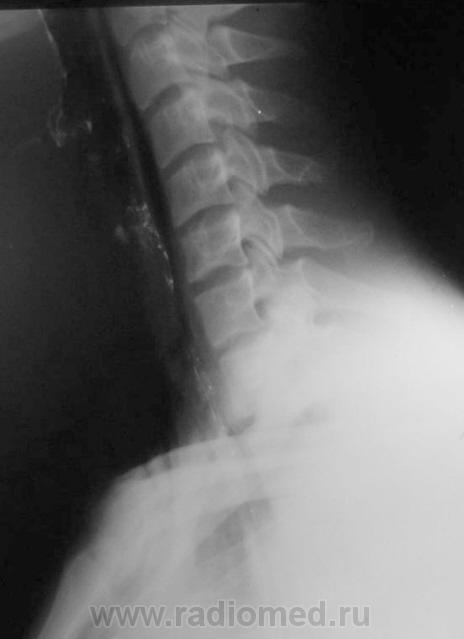

Шейный кифоз настораживает.Отсутствие легочного рисунка в верхней доле левого легкого с краем легкогоЭмфизема мягких тканей шеи..Согласна с коллегой.Пару лет назад по кифозу ШОП, увеличению превертебрального пространства и столбу воздуха поставили разрыв пищевода.Дали  контраст-подтвердили.

Затекания контраста за пределы пищевода на представленных рентгенограммах не выявлено. Нет фазы тугого заполнения. Левосторонний пневмоторакс.

Да, ЛОРа 100% надо на консультацию, т.к. барий затек не туда.